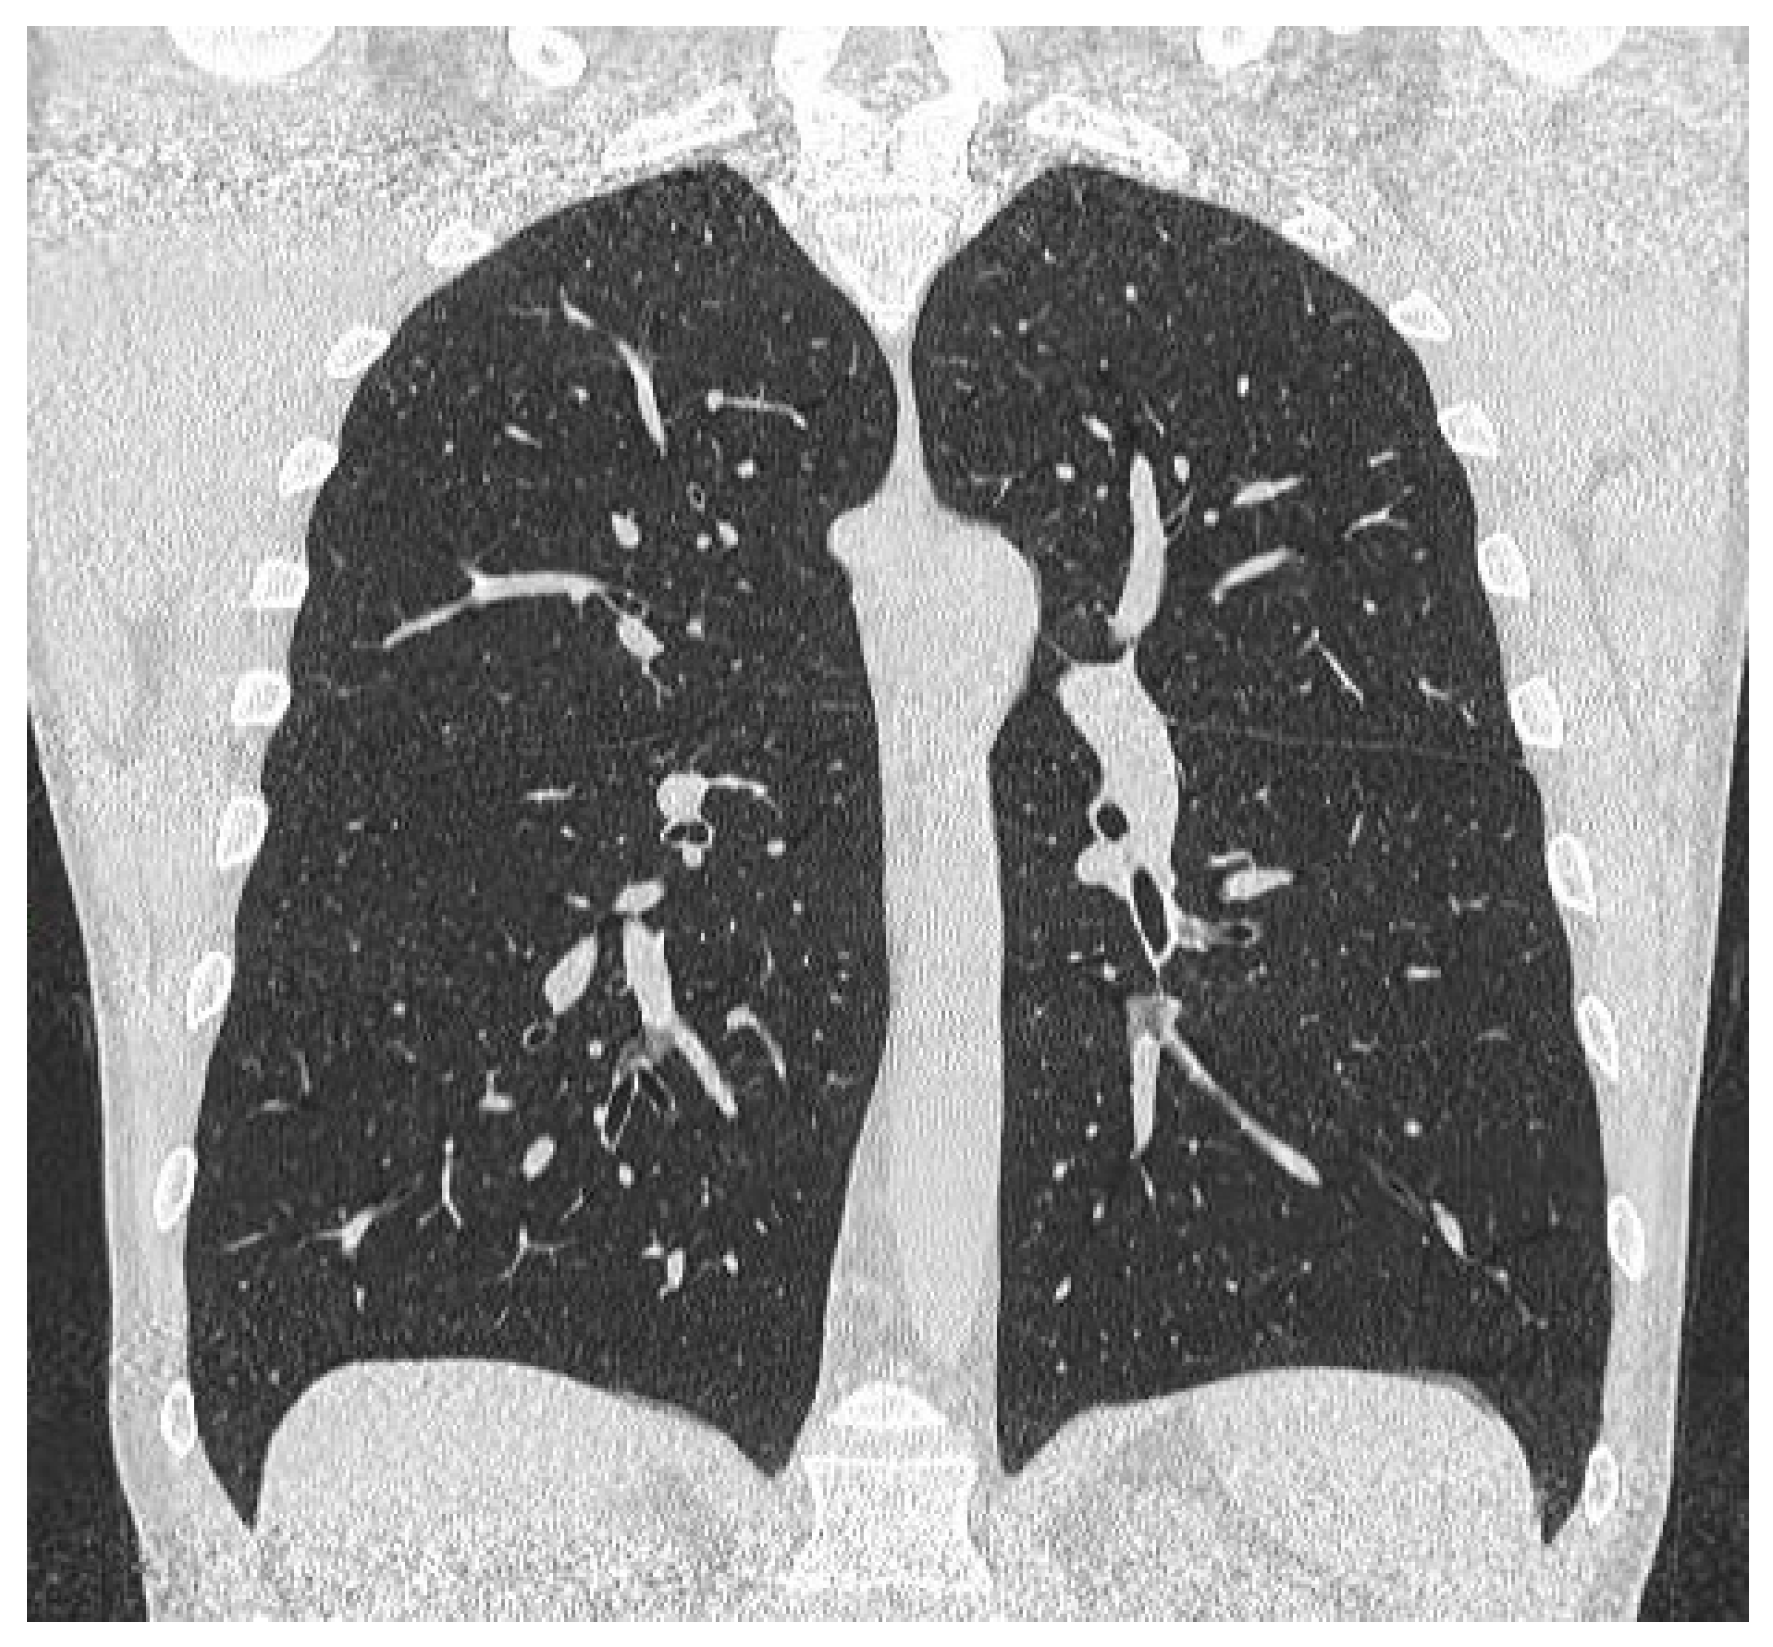

Figure 1.

Coronal reconstruction of the unenhanced chest CT scan performed in 2021 during the SARS-CoV-2 infection. Diaphragms are symmetrical without any signs of elevation.